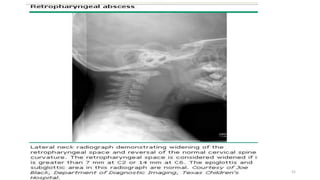

RETROPHARYNGEAL ABSCESS

• May extrinsically compress structures in the upper airway.

RETROPHARYNGEAL ABSCESS CONT…

• Examination of the pharynx can reveal bulging of the posterior wall.

• Widening of the retropharynx is seen on a lateral neck radiograph.

• Surgical drainage and broad-spectrum IV antibiotics are required.

• Intubation may be needed to protect the airway during the acute

phase of the illness.